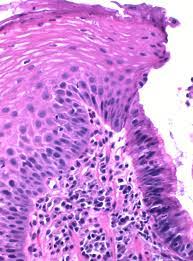

위식도 역류성 질환은 위 내용물이 소량씩 식도로 역류하고, 이러한 역류의 과정이 반복되어 식도 점막이 손상되어 염증이 나타나는 질환을 의미합니다. 이는 위와 식도 사이에서 위의 내용물이 식도로 올라오는 것을 막아 주는 조임쇠 역할을 하는 괄약근에 이상이 생겨 발생합니다.